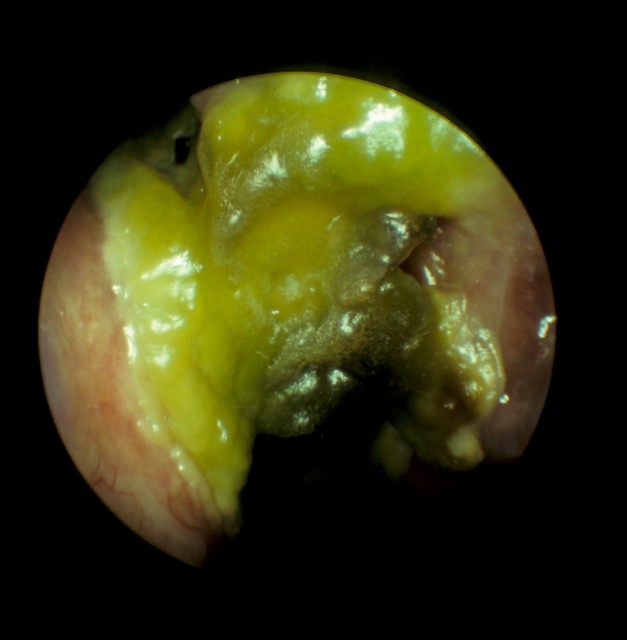

Greenish yellow crusts seen inside the nasal cavity of a patient with atrophic rhinitis

Clinical examination of these patients show that their nasal cavities filled with foul smelling greenish, yellow or black crusts, the nasal cavity appear to be enormously roomy. When these crusts are removed bleeding starts to occur.